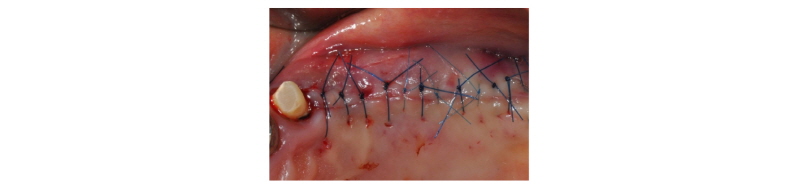

70세의 여자환자로 상악에 사용하던 부분틀니가 불편하다고 호소하시며 내원하였다. 부분 틀니의 지대치인 상악 좌측 견치 또한 보철물 하방으로 우식이 진행되어 보철물 제거후 우식치료 후 보철물을 재제작하여 장착하기로 계획하였다. 치아가 결손되어 있던 상악 좌측 소구치와 대구치 부위는 임플란트 식립(#24i-26i, 27i)을 통한 고정성 보철물 수복을 계획하였다(Fig. 19). 장기간의 부분틀니 장착으로 인해 임플란트 식립 예정 부위의 심한 치조제 흡수가 관찰되었으며 특히 소구치 부위가 가장 흡수 정도가 심하였다(Fig. 20). 전층판막 형성 후 상악 좌측 제 1 소구치 부위는 치조정에서 약 2 mm 정도의 매우 좁은 치조제 폭경이 확인되었다(Fig. 21). 먼저 상악 좌측 제 1 소구치 부위 치조정에 horizontal intraosseous groove를 작게 형성한 후 협측골에 근, 원심 양측에 vertical intraosseous groove를 형성하였다(Fig. 22). Chisel을 이용하여 협측 골판을 조금 확장시킨 다음 spreader drill (RS kit, Dentium, Korea)을 단계적으로 이용하여 충분히 확장시켜 임플란트 식립을 위한 공간을 확보하였다(Fig. 23). 분리된 협,설측 골판 사이 공간으로 Ø4.3 × 10 mm (Implantium, Dentium, Korea) 임플란트를 식립하였다(Fig. 24). 상악 좌측 대구치 부위는 상악동 거상술(측방접근법)을 시행하여 #26i, 27i : Ø4.3 × 10 mm, Ø4.8 × 10 mm (Implantium, Dentium, Korea)를 식립하였다(Fig. 25). 식립된 24i 임플란트와 협,설측 골판 사이의 gap에 합성골 (Osteon II, Xenoss, Korea)을 적용한 다음 협측 골판 상방에 콜라겐함유 합성골(Osteon II Collagen, Xenoss, Korea)을 추가적으로 적용하였고 식립된 26i, 27i 임플란트 부위의 협측골 두께가 얇아서 협측골 상방에도 콜라겐함유 합성골(Osteon II Collagen, Xenoss, Korea)을 적용하였다(Fig. 26). 골이식재 상방에 흡수성 교원질 차폐막(Collagen, Xenoss, Korea)을 피개한 후 감장절개를 통해 장력없이 봉합하였다(Fig. 27, 28). 약 10일 후 발사 시의 임상소견으로 정상적으로 치유가 잘 진행되었다(Fig. 29). 술 후 파노라마 방사선 소견으로 치조제 분할술을 통해 식립된 24i 임플란트와 상악동 거상술(측방접근법)을 시행하여 식립된 26i, 27i 임플란트가 확인되었다(Fig. 30). 4개월 치유 후 이차 수술 시 전층 판막거상 후 협측으로 충분히 증가된 치조제 폭경과 식립된 임플란트 주위에 이식한 골이 혼화되어 치유된 양상이 확인되었고 치유지대주를 연결하였다(Fig. 31). 이차 수술 후 치유가 정상적으로 진행되어 통법에 따라 보철 수복하였다. 보철물 수복 직후 방사선 사진 소견으로 식립된 24i 임플란트의 변연골 위치가 확인되었다(Fig. 32). 보철물 장착 후 1년 후 방사선 소견에서 임플란트 주위 변연골이 안정적으로 잘 유지되고 있었다(Fig. 33). 보철물 장착 4년 후 follow- up 결과 임플란트 주위 치은이 약간 퇴축된 양상을 보였으나 임상적으로 특이한 소견이 관찰되지 않았고 방사선 소견에서 임플란트 주위 변연골이 안정적으로 잘 유지되고 있음을 확인하였다(Fig. 34-36).

|

Fig. 28. Flap was closed with tension-free sutures. |